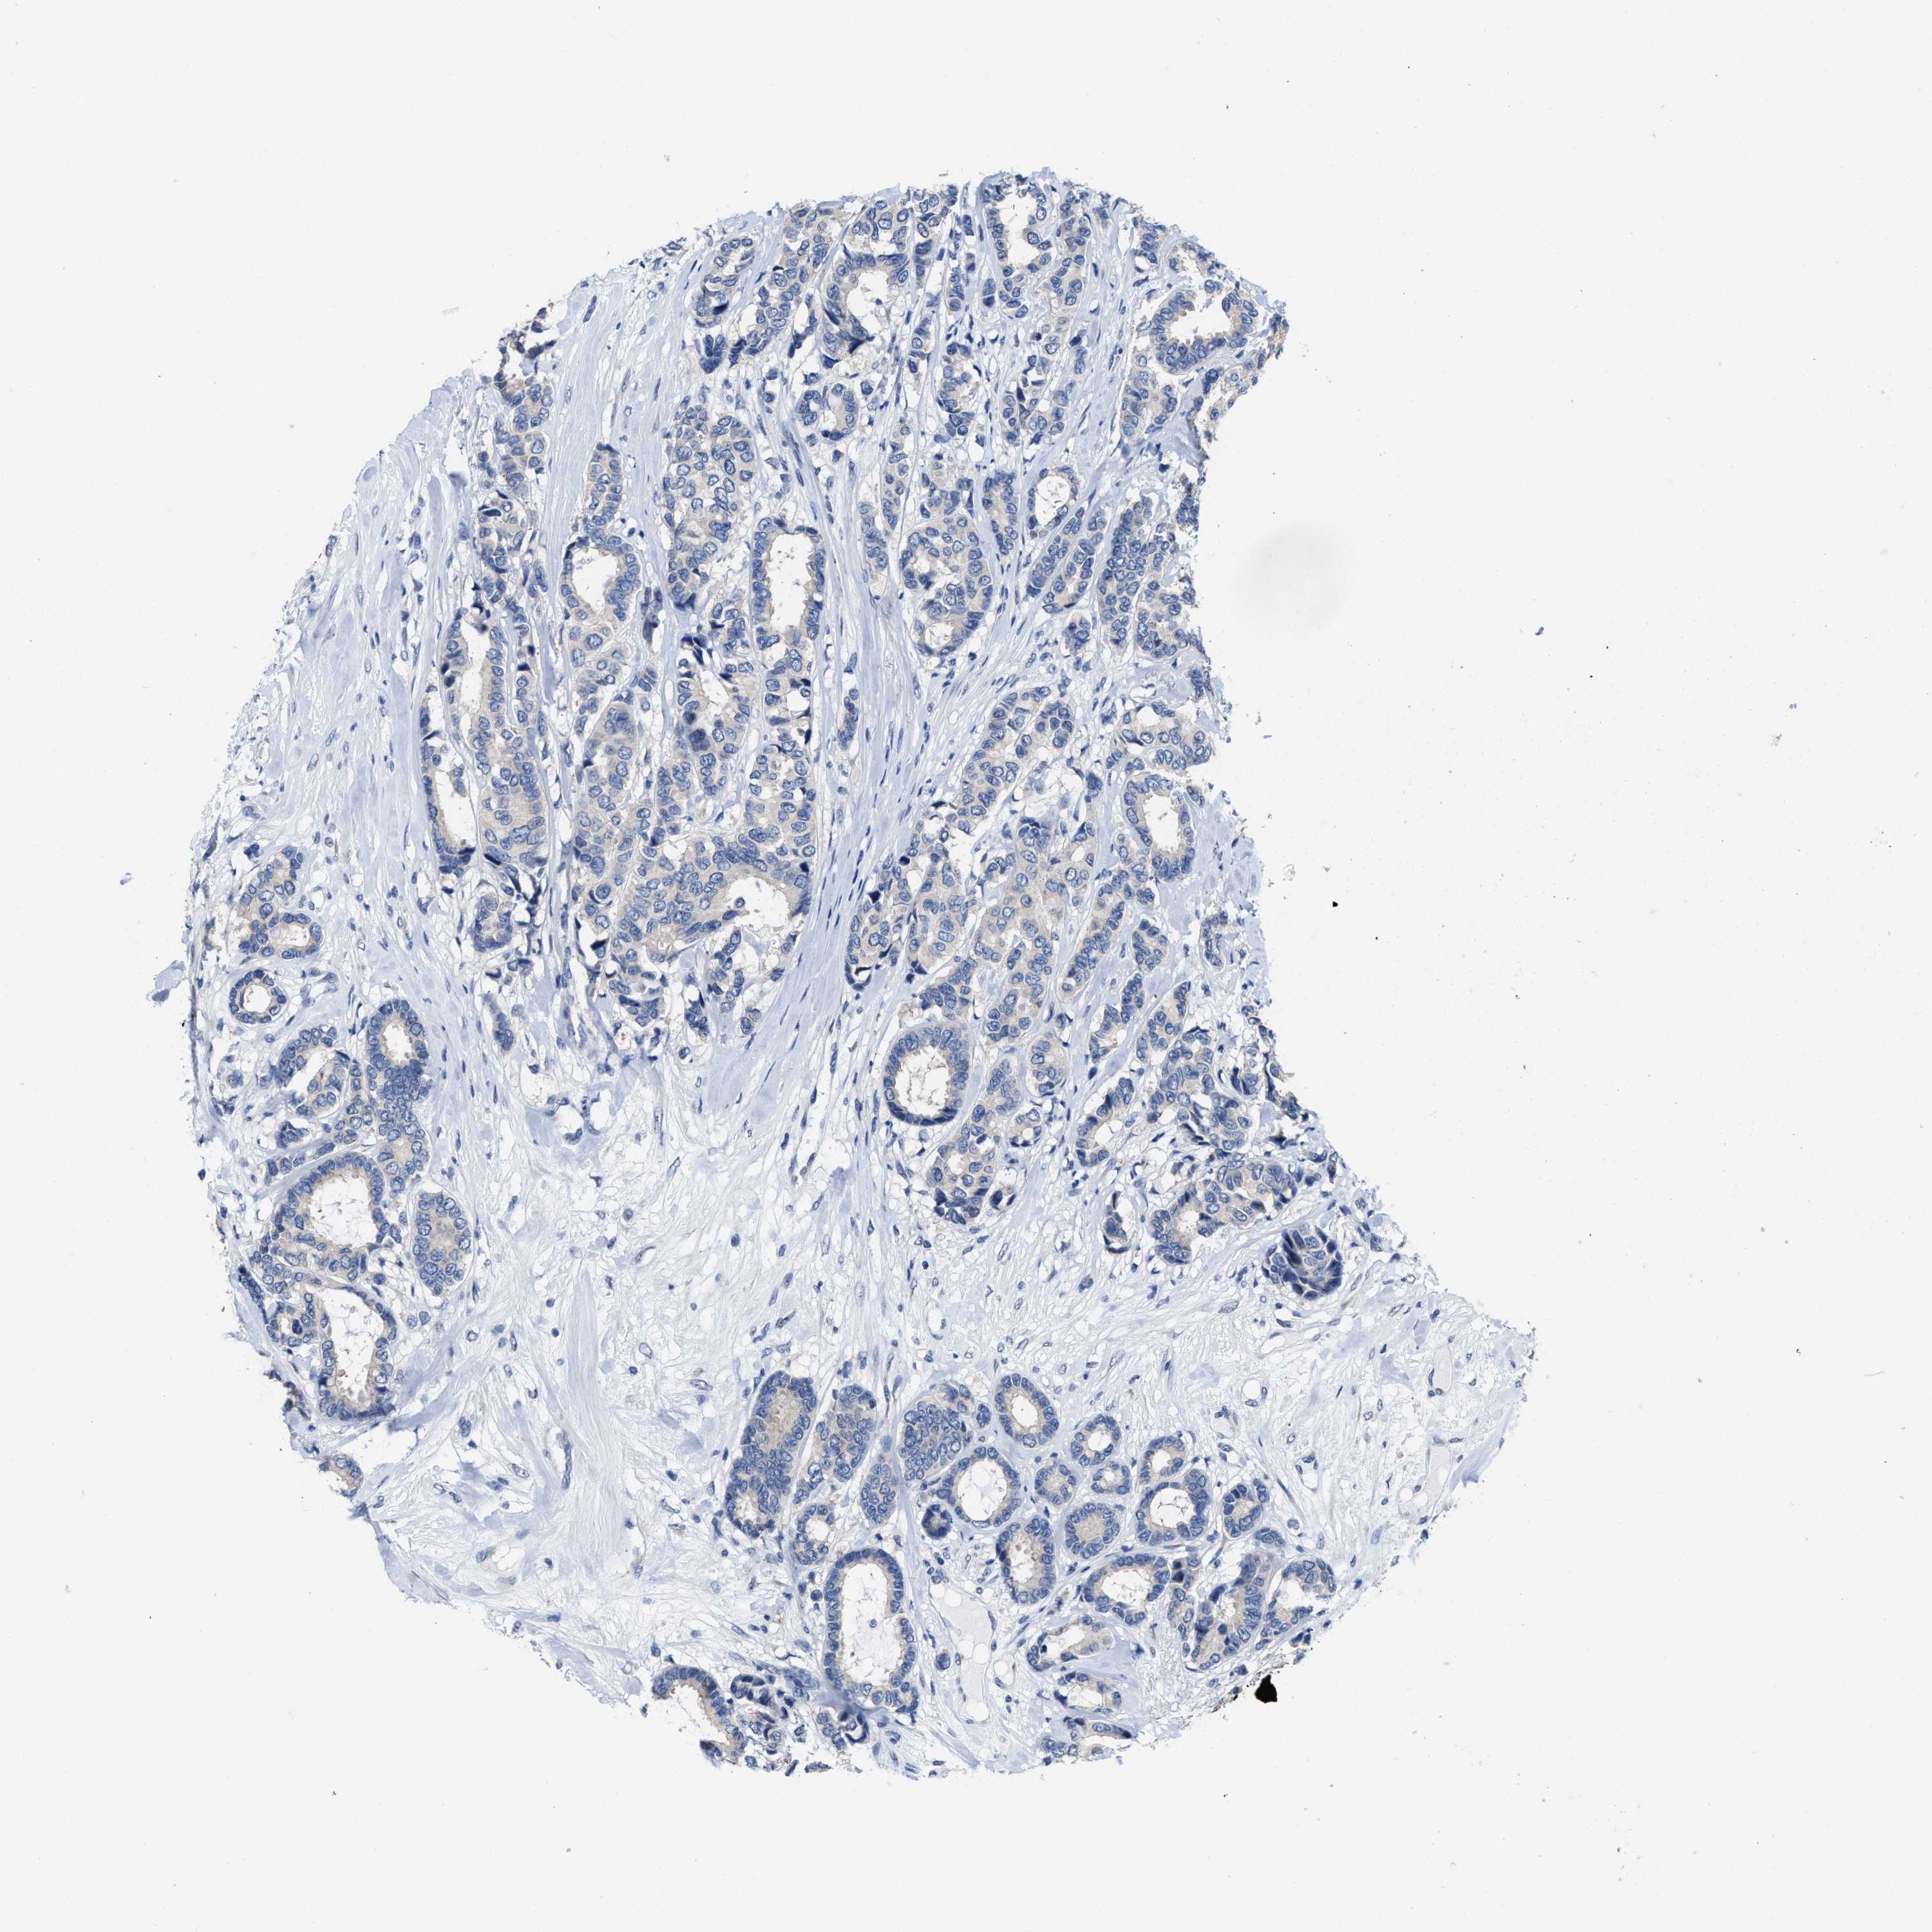

CANCER BREAST CANCER Show tissue menu

BRCA TCGA BRCA VALIDATION PROTEIN EXPRESSION

Breast cancer

Human cancer

HOOK1 is not prognostic in Breast Invasive Carcinoma (TCGA)